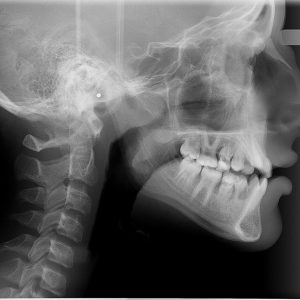

Методы диагностики и лечения

Перед принятием решения о методах лечения необходимо удостовериться в наличии прободения костной перегородки. Это можно сделать, используя миниатюрный зонд, рентген или компьютерную томографию. При проведении рентгенологического исследования обязательно используют контрастное вещество. Полученное изображение позволит определить наличие инородных объектов или сгустков крови в гайморовой пазухе.

Иногда дефект в носовой перегородке бывает настолько древним, что его можно выявить только с помощью медицинских исследований и компьютерной томографии.

Рентген носовых пазух может предоставить значительную помощь. Если на изображении видны темные участки в полости, это может указывать на наличие скопления крови внутри. Также на рентгеновском снимке можно увидеть обломки корней зуба, расположение штифтов и материал, выступающий изнутри канальной пломбы. Для разрешения сомнений может быть полезна рентгенография с применением контрастного вещества.

Одним из недостатков рентгеновских изображений является их плоскость. Получение трехмерного изображения становится возможным при проведении компьютерной томографии. Медицинский специалист проанализирует полученные сканированием данные с помощью специальной программы, осмотрит зуб с различных ракурсов и разработает индивидуальный план лечения.

При таких обстоятельствах результаты носовой пробы и контрольной пробы могут оказаться отрицательными. Положение корня определяется при помощи рентгеновского снимка.